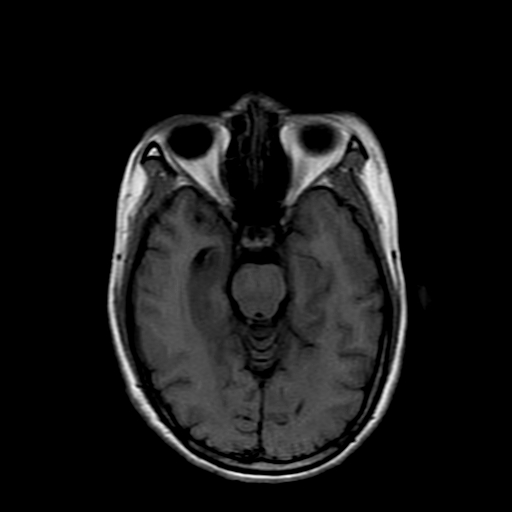

女性,47岁。mri号03027,外伤致头痛9天,抽搐一天,原无类似病史。

dwi及矢状位无明显异常,所以没发。

双侧海马的信号都有异常。

双侧海马硬化!

颞叶前部萎缩,海马萎缩,t2wi海马高信号,支持海马硬化。

双侧海马硬化.

双侧海马区t1低,t2高信号。为什么都考虑硬化?发病原因?鉴别诊断:炎症,梗塞等能一下子除外吗?